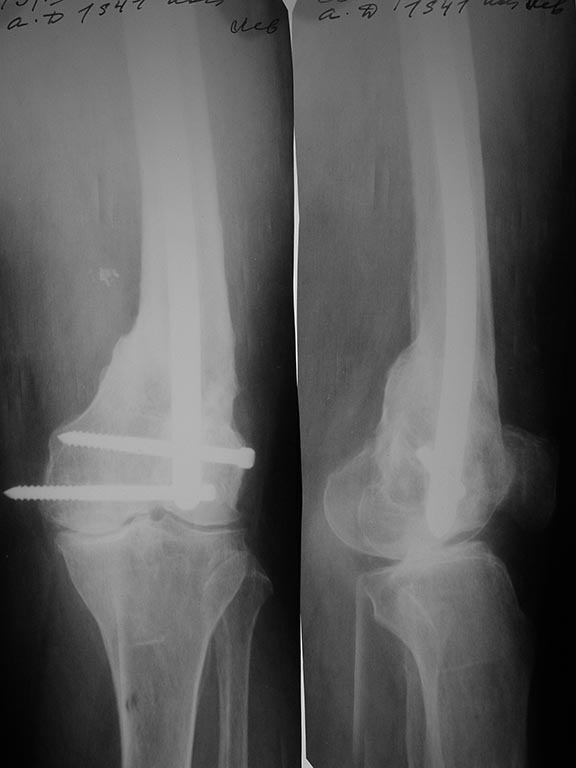

Вот давний пример похожего ложного сустава после неоднократных

остеосинтезов.